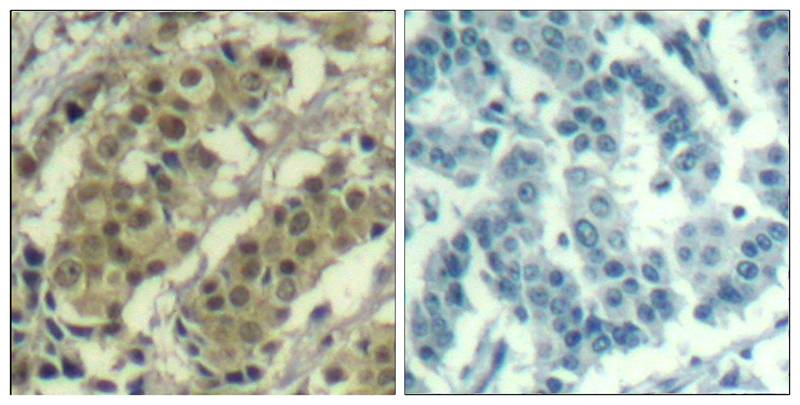

- Immunohistochemical analysis of paraffin-embedded human breast carcinoma tissue using AKT1(Ab-450) Antibody P41539(left) or the same antibody preincubated with blocking peptide(right).